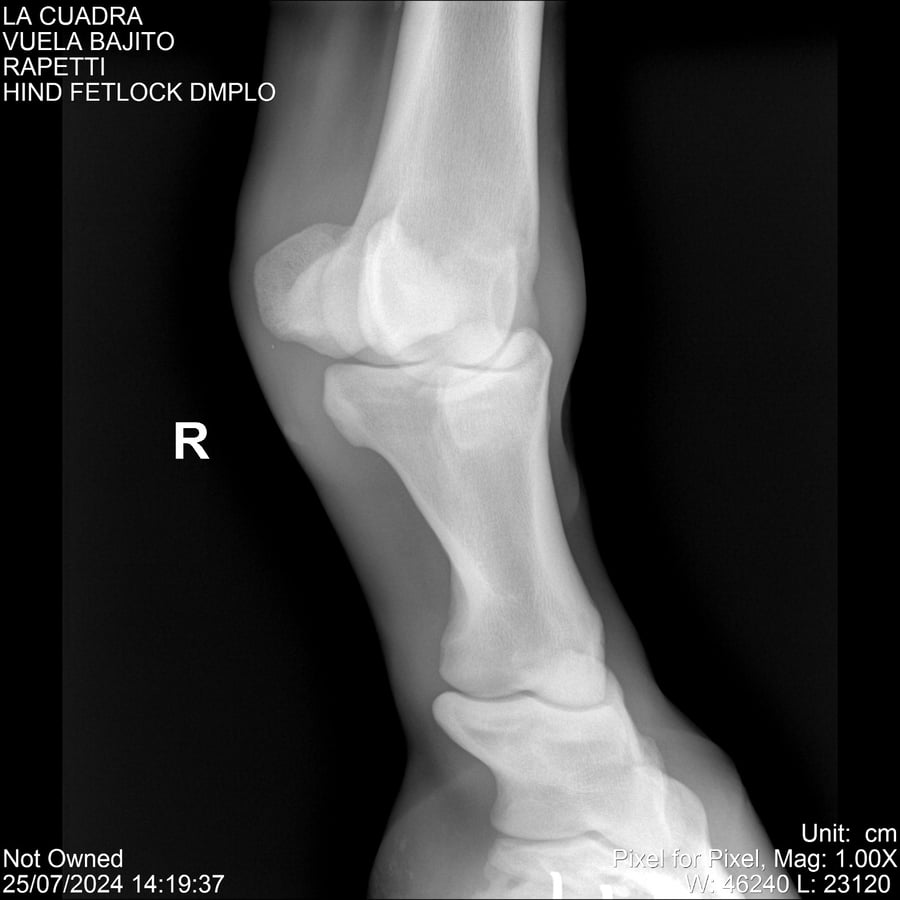

LOTE 16, VUELA BAJITO Lote Anterior Volver al remate Lote Siguiente Ficha Contacto Montevideo - Ficha del Lote Identificador: #284451 Categoría: Yeguarizos Montevideo - 77 Visualizaciones ClicData Contacto Empresa: Abelenda N. R., Walter Hugo Nombre*: Teléfono* : E-mail* : Mensaje Enviar Registrese gratis Este contenido Exclusivo está disponible sólo para usuarios registrados Ingresar